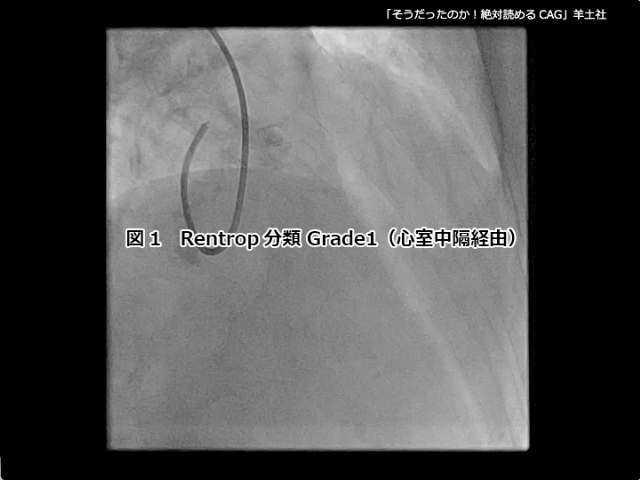

そうだったのか! 絶対読めるCAG【付録動画サンプル】